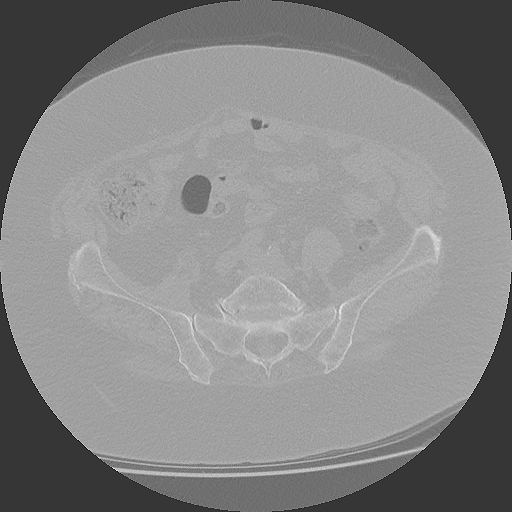

04.03.2025

CT Becken

853 Bilder in 4 Serien | 86 MB

März 2025

CT Becken + Überweisung

CT-Untersuchung mit Befund, Überweisung zur weiteren Behandlung

DICOM

CT-Untersuchung mit 4 Serien (853 Bilder)